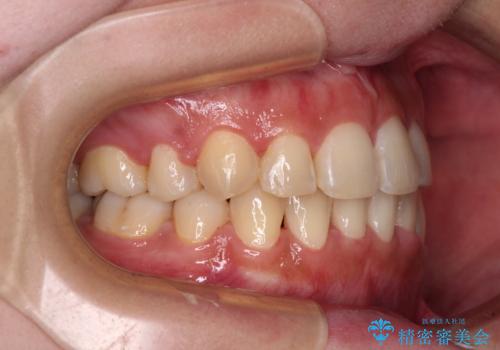

- 八重歯やデコボコをインビザラインで治療したいとのことで来院された患者様です。

インビザライン単体で治療を行うには叢生が強いと判断されたため、事前にワイヤー装置で抜歯矯正を行い、ある程度改善してからインビザラインにて仕上げていくこととしました。

- 4年5ヶ月